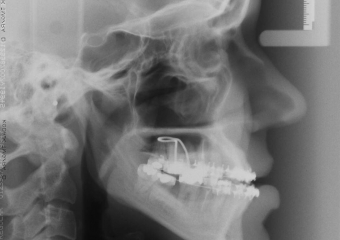

Telerradiografia final - Clínica Cliniface

Telerradiografia final